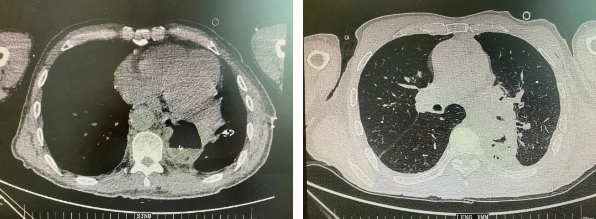

患者王某不幸同時(shí)患食管癌與左肺癌,病理類型系雙源發(fā)腫瘤,食管為鱗癌、肺為腺癌。食管癌和肺癌為胸外科最常見的疾病,但同時(shí)患兩種疾病,十分罕見。家屬輾轉(zhuǎn)多個(gè)醫(yī)院,得知李小飛院長(zhǎng)擅長(zhǎng)胸外科復(fù)雜手術(shù),慕名來(lái)西安國(guó)際醫(yī)學(xué)中心醫(yī)院。

經(jīng)過(guò)李小飛教授、李文海副教授、穆強(qiáng)副主任醫(yī)師團(tuán)隊(duì)積極準(zhǔn)備,排除手術(shù)禁忌;經(jīng)過(guò)全科術(shù)前充分討論,大家認(rèn)為:如果分兩次進(jìn)行手術(shù),另一種疾病勢(shì)必會(huì)受到影響,腫瘤可能進(jìn)展。胸外科手術(shù)對(duì)呼吸循環(huán)影響較大,同期實(shí)施兩個(gè)手術(shù)更要小心謹(jǐn)慎。李小飛教授主持術(shù)前討論,設(shè)計(jì)合理手術(shù)方式,由于食管癌胸腔鏡手術(shù)為右側(cè)入路,但為兼顧左肺癌手術(shù),則采用傳統(tǒng)左開胸手術(shù)。

2022年4月25日,由李小飛教授主刀,同期行左側(cè)開胸:食管癌根治術(shù) 左肺癌根治術(shù),一次手術(shù)同時(shí)根治兩種惡性腫瘤疾病。經(jīng)過(guò)精細(xì)手術(shù)及術(shù)后管理,患者術(shù)后十天,恢復(fù)良好,進(jìn)食良好,現(xiàn)已出院。